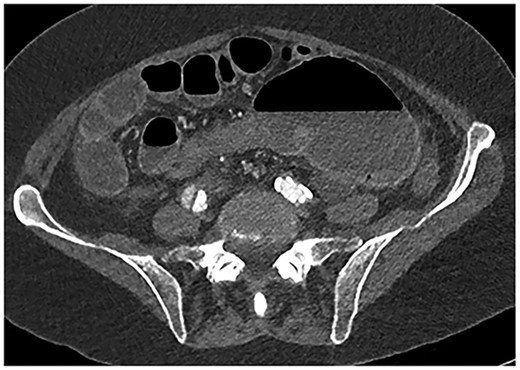

A 61-year-old female with known Marfan Syndrome was admitted to the emergency department with 3-day history of abdominal pain, nausea, vomiting and bowels not opening. Past medical history included three previous episodes of Type A aortic dissection, recent aortic root and ascending aorta replacement alongside bioprosthetic aortic valve replacement. She was an ex-smoker and usually independent at home. On presentation, the patient was haemodynamically stable and apyrexial. Biochemical results were unremarkable except for a Lactate dehydrogenase (LDH) of 309 and a C-reactive protein (CRP) of 101. On examination, she had a diffusely tender and distended abdomen, without signs of peritonism. An erect chest X-ray shows left pleural effusion with a dilated aortic root (Fig. 1). A computed tomography (CT) of thorax, abdomen and pelvis was requested, which demonstrated a caecal volvulus with a dilated cecum of 8.8 cm and upstream small bowel dilatation with air fluid levels, and a chronic aortic dissection extending from the ascending thoracic aorta to the common iliac (Figs 2–4). Following consultation between radiologists, cardiothoracic surgeons and general surgeons, she underwent an emergency laparotomy and right hemicolectomy with side-to-side ileocolic anastomosis. Intraoperatively, the caecal volvulus, comprising a dilated ascending colon measuring up to 10 cm, was delivered and resected along with its mesentery. The patient was admitted to the intensive care unit post-operatively for close blood pressure monitoring and control and stepped down to level 3 wards on day-2 post-operation. Her operation was complicated by a small infected wound haematoma thatwas managed with a 5-day course of ciprofloxacin. A CT of the abdomen and pelvis to investigate a rising CRP on day-9 revealed a subcapsular liver haematoma thath was managed conservatively. The patient was discharged 12-days post-operatively. Histology from the resected colon showed evidence of ischaemia in keeping with a closed loop obstruction such as caecal volvulus. There was also an incidental T1 N0 colonic tumour arising from a sessile serrated polyp and two other serrated polyps. A colonoscopy to inspect the remaining colon has been arranged.

CT abdomen axial view demonstrating the Beaking sign—a progressive tapering of afferent and efferent limbs leading into the twist.